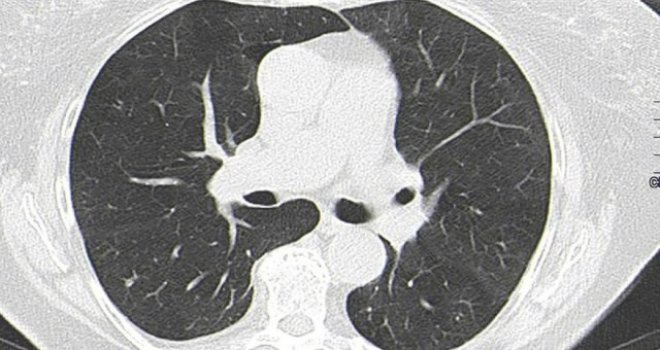

2019'un sonunda ortaya çıkan corona virüsünün mutasyona uğramış hali uluslararası kamuoyunda panik yaratmaya devam ediyor... İngiltere'nin saygın kurumlarından Imperial College London, mutasyona uğramış corona virüsünün en çok 20 yaş altındakileri hedef aldığını duyurdu.

Bir yılı aşkın bir süredir 83 milyondan fazla insana bulaşan corona virüsü, son haftalarda mutasyona uğramış yeni bir salgın paniği yarattı. Mutasyona uğramış corona virüsü ile ilgili birçok çalışma yapılırken, bu tür virüsün ilk tespit edildiği ülke olan İngiltere’de yapılan bir araştırma bu virüsün etkisini ve yaratabileceği tahribatı gözler önüne serdi.

Imperial College London başta olmak üzere ülkedeki bazı sağlık kuruluşlarının dahil olduğu araştırmaya göre, normal Covid-19’a göre daha çabuk yayılan bu virüsün özellikle 20 yaşın altındakileri daha çok etkilediği tespit edildi.